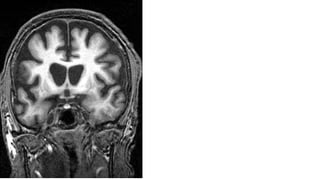

RADIOGRAPHIC FEATURES

The frontal and temporal lobes are predominantly affected, there is

often striking asymmetry both of involvement of frontal vs temporal

lobes, and involvement of left and right hemispheres.

In addition the degree of fronto-striatal dysfunction varies between

the different FTLD subgroups, with behavioural variant

frontotemporal dementia (bvFTD) having the greatest involvement.

As a result the caudate heads tend to be reduced in size in these

patients, to a much greater degree than in the language variants of

frontotemporal dementia.

MRI

typical radiographic finding is atrophy of the frontal lobes and, to a

lesser extent, the temporal lobes.

The degree of atrophy can be very asymmetric

Decrease in volume of the caudate heads. This indicates loss of both

efferent and afferent fibres.